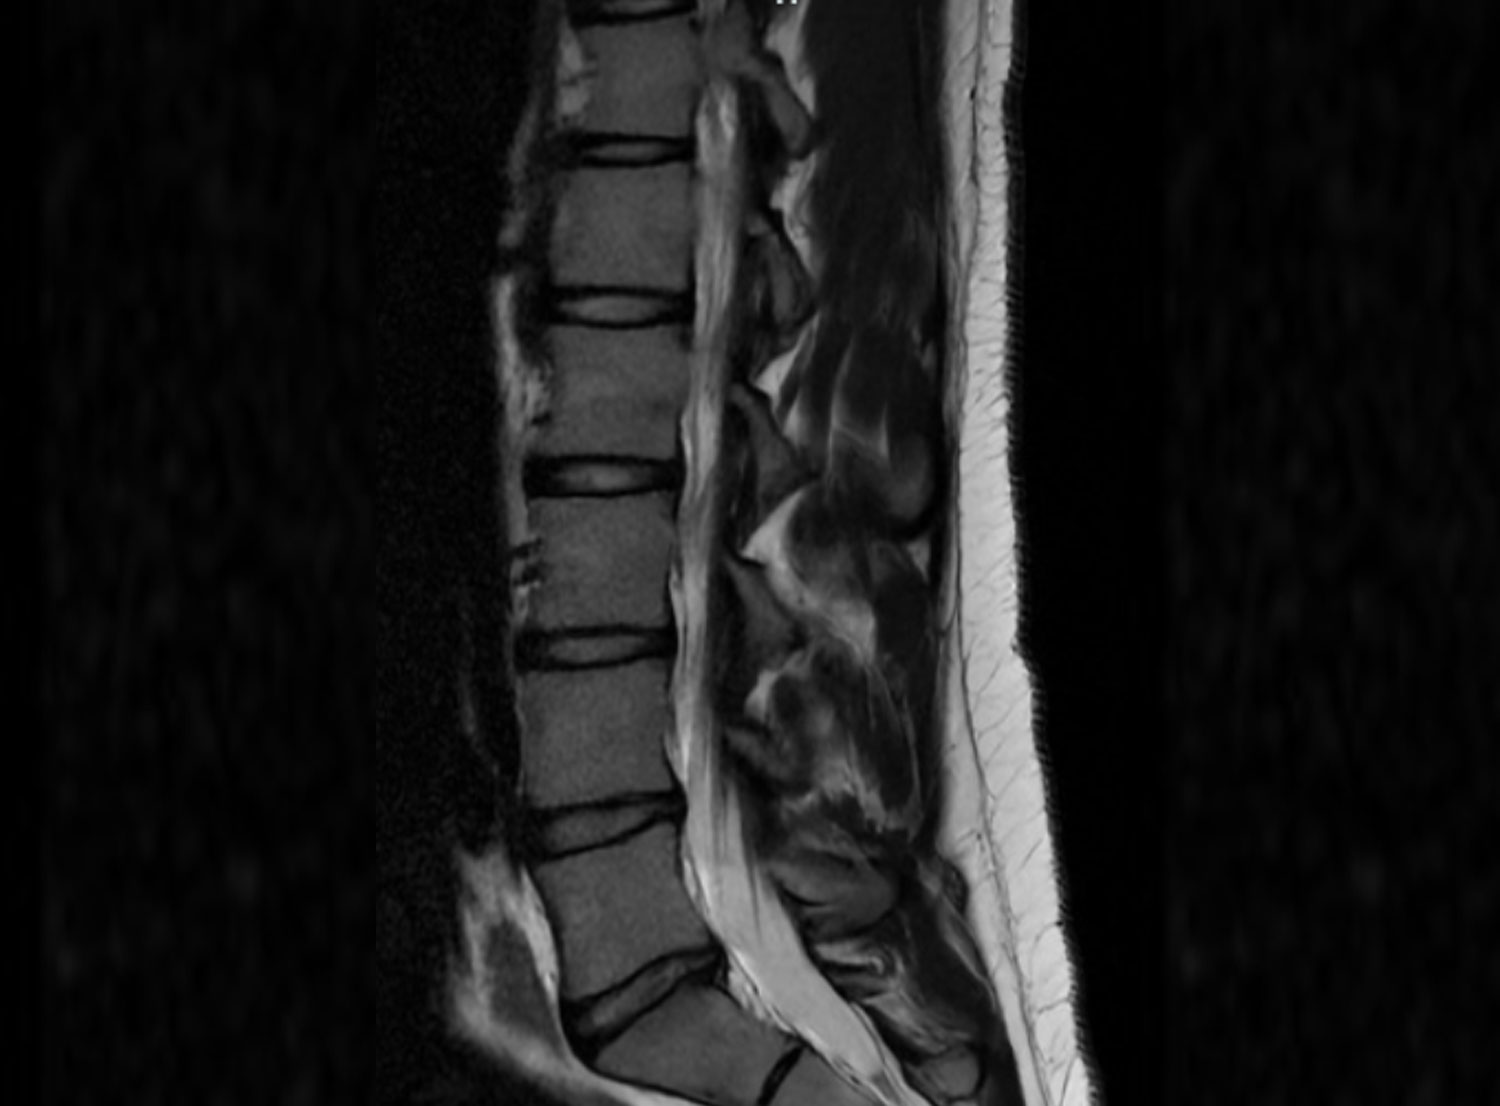

Die MRT der Wirbelsäule und der Rückenmarksflüssigkeit (auch bekannt als MRT-Myelographie), dient der Beurteilung der Bandscheiben und der Darstellung von Stenosen, Raumforderungen oder Zysten im Bereich des Spinalkanals. Die Myelographie ist eine schonende bildgebende Technik, die es ermöglicht, den Rückenmarkskanal sowie die Rückenmarksflüssigkeit des Duralsacks mithilfe der Magnetresonanztomographie (MRT) darzustellen. Im Gegensatz zur konventionellen Myelographie erfordert die MR-Myelographie keine Punktion des Liquorraums zur Einbringung eines Kontrastmittels.

Die MRT-Myelographie verwendet spezielle Flüssigkeit sensitive Sequenzen der Magnetresonanztomographie (MRT), um die Nervenstrukturen des Rückenmarks und des umgebenden Gewebes sichtbar zu machen. Im Unterschied zur herkömmlichen Myelographie hat sie den Vorteil, dass keine Punktion des Liquorraums und keine Kontrastmittelgabe erforderlich ist.